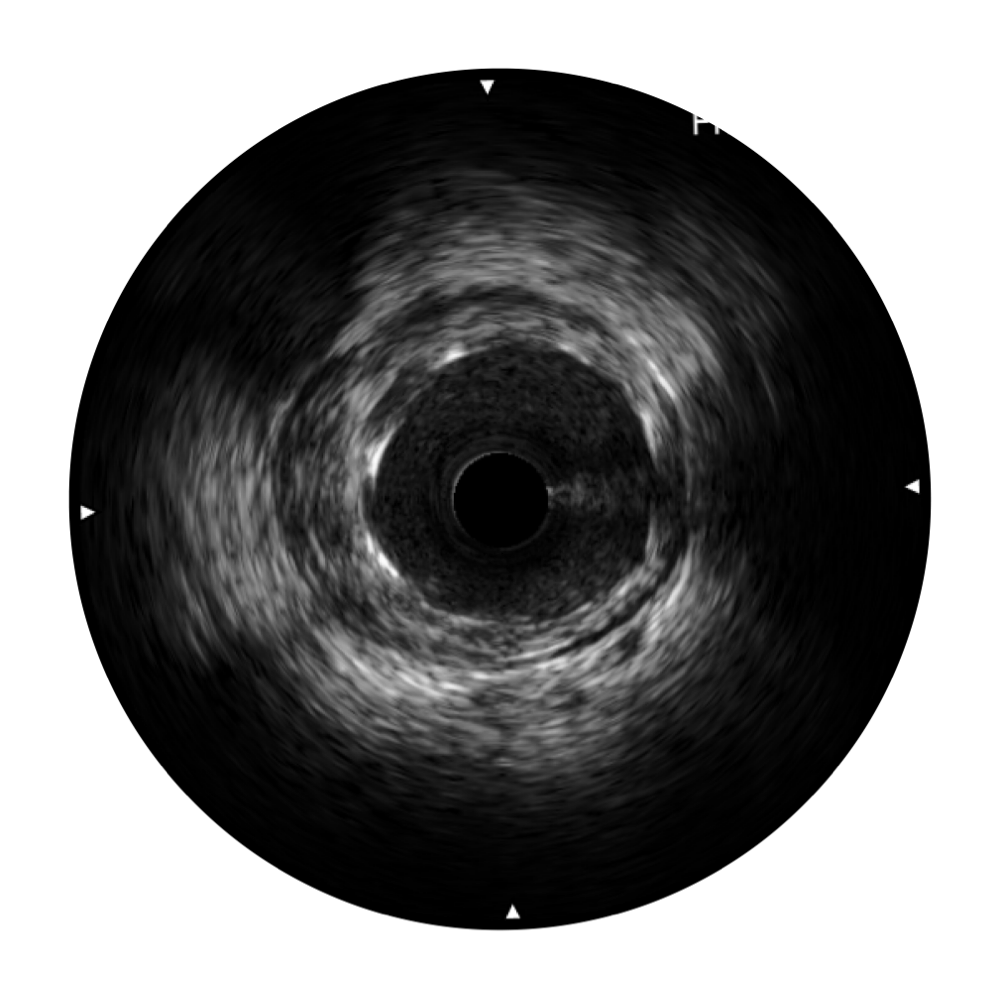

血管内超声(IVUS) 通过对病变程度、性质和累及范围的精确判断,可帮助选择治疗策略和方法,指导介入治疗过程,能够降低主要不良心血管事件,改善预后,在复杂病变介入治疗中用于指导支架置入的优势更为明显。血管内超声(IVUS)已成为精准心血管介入治疗的“金标准”。

玖鼎集团始终关注未满足的临床需求:超宽频成像技术同时提供高清分辨力和充足穿透深度,适应不同血管结构的治疗引导;智慧赋能,简化操作,降低临床应用难度和缩短学习曲线。